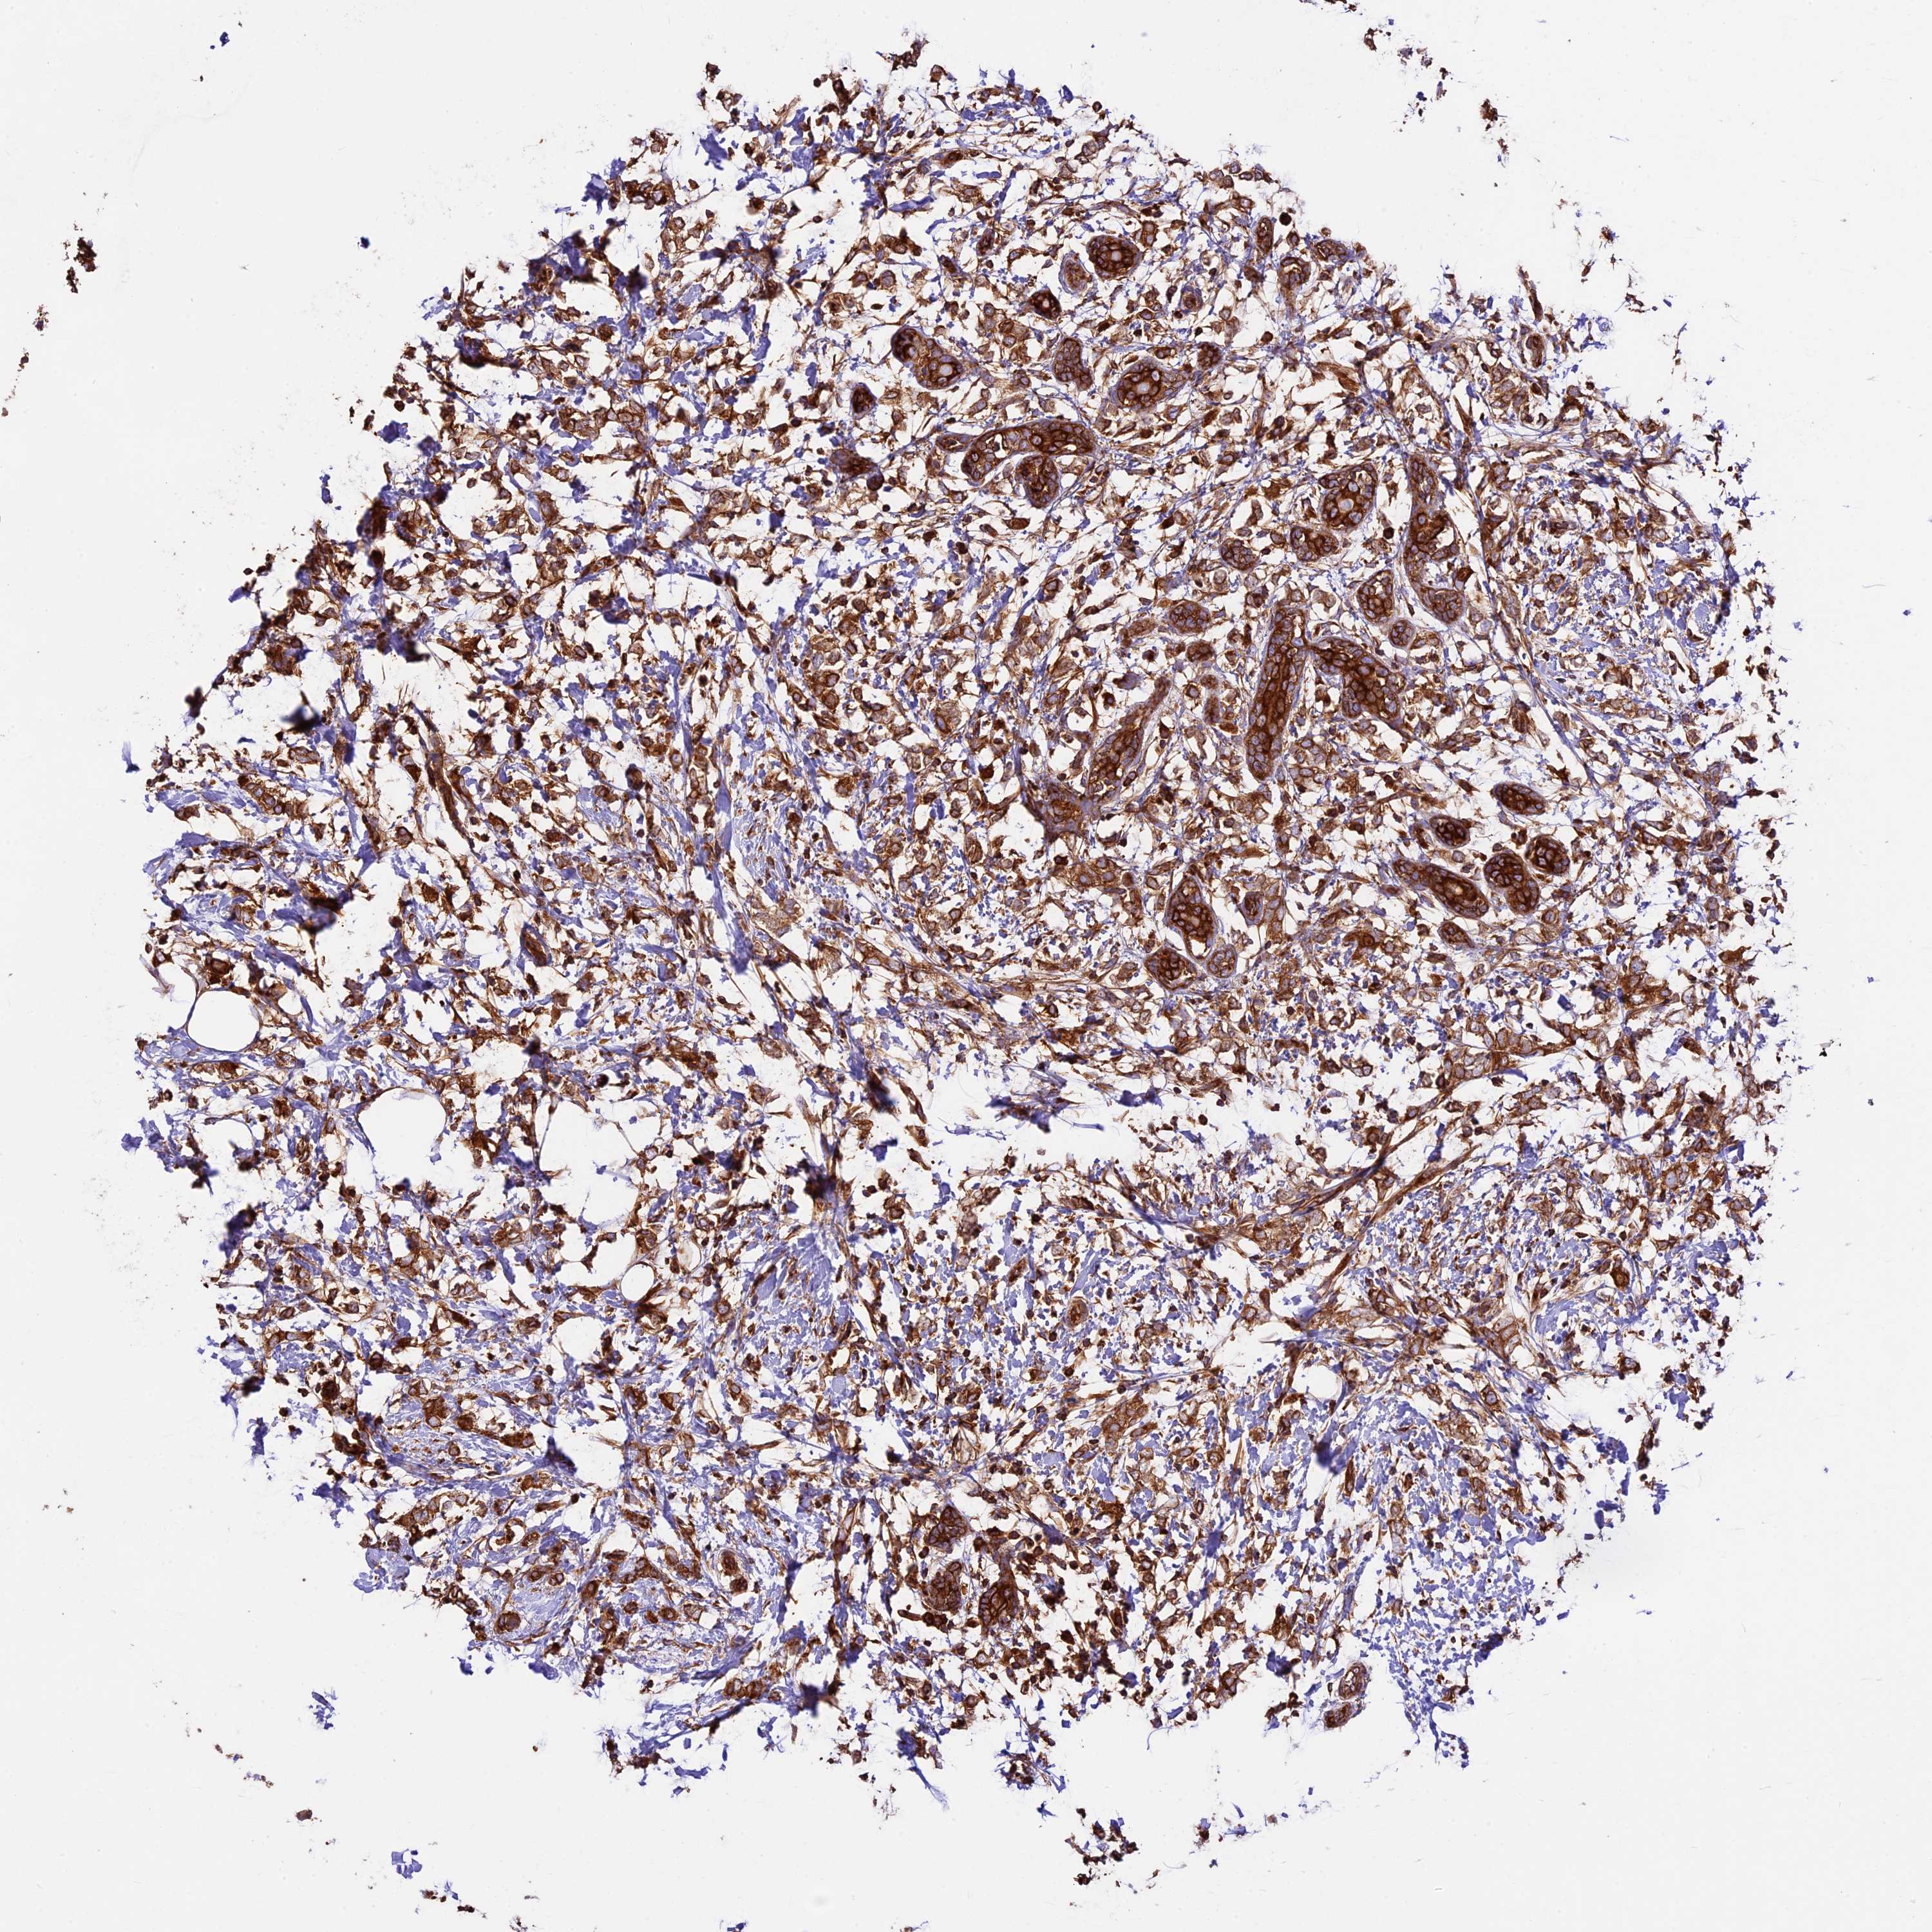

CANCER BREAST CANCER Show tissue menu

BRCA TCGA BRCA VALIDATION PROTEIN EXPRESSION

Breast cancer

Human cancer